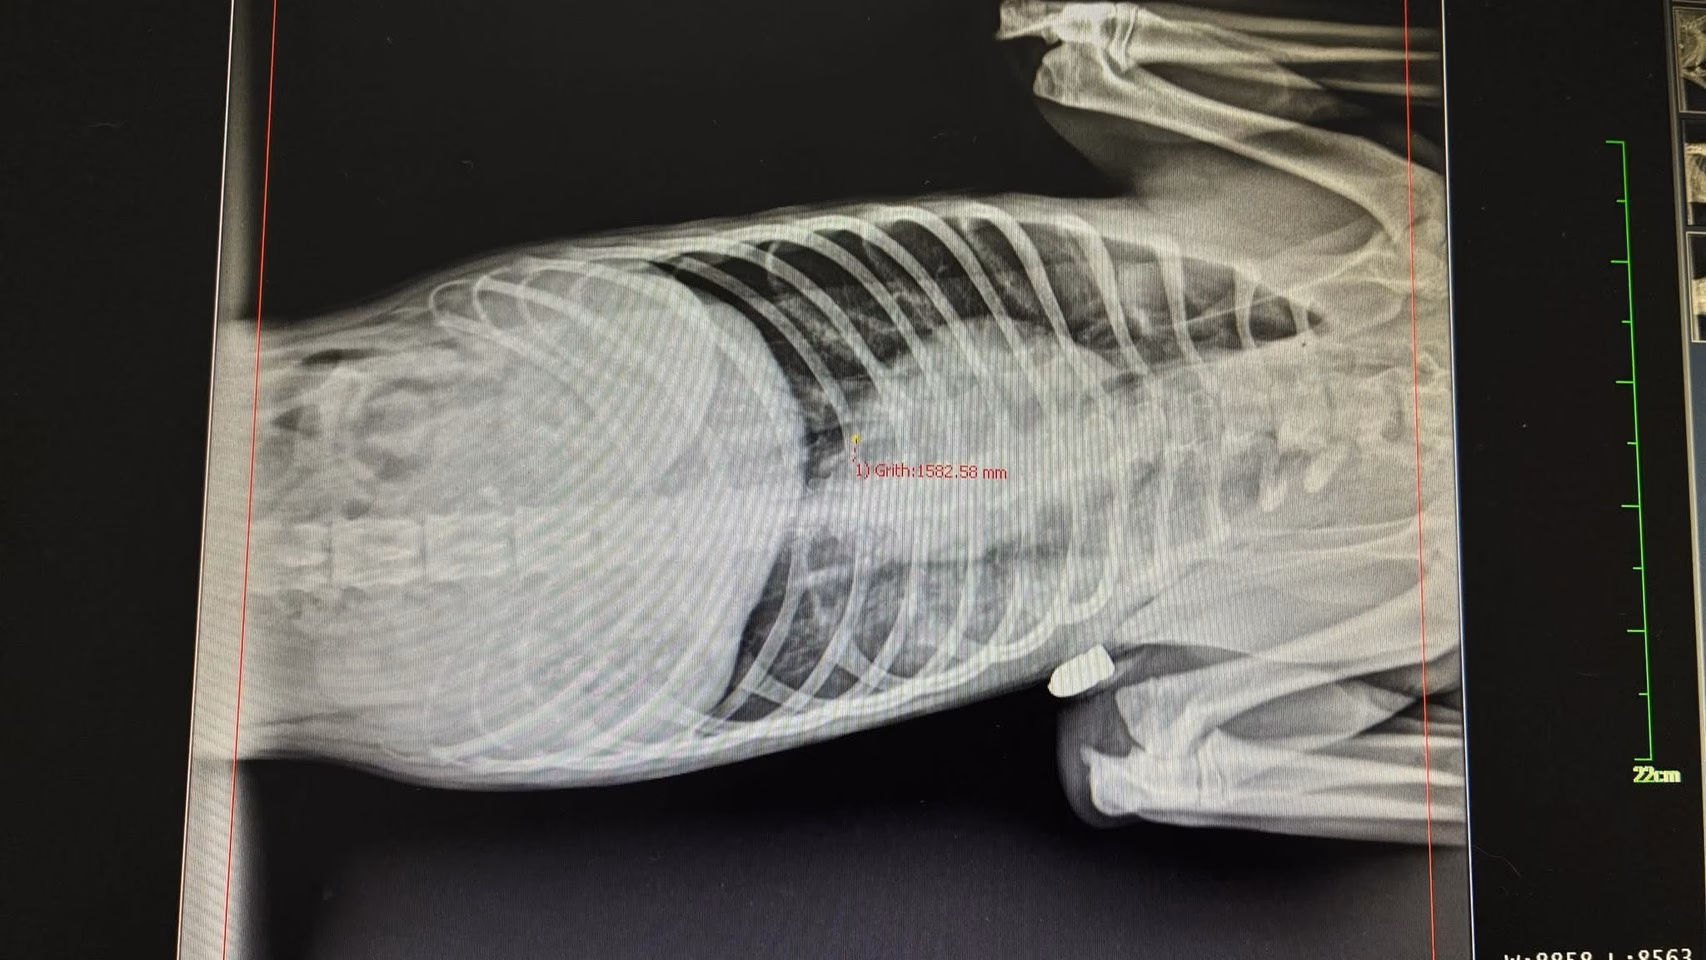

ผลการตรวจเอกซเรย์ของสัตวแพทย์ พบลูกกระสุนฝังอยู่บริเวณรักแร้ใต้ขาหน้าด้านขวา โดยวิถีกระสุนพุ่งจากด้านหน้า ทะลุผ่านลิ้น ลำคอ และไปฝังบริเวณซี่โครงด้านขวา สร้างความเสียหายอย่างรุนแรงต่อร่างกาย